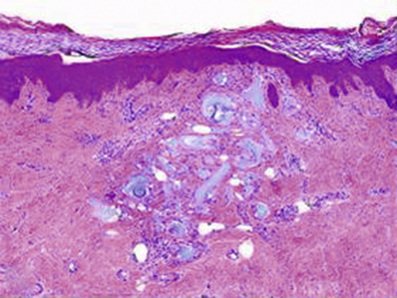

• Collagen IV immunostaining (stains the BMZ)

■ Performed on paraffin embedded sections to determine level of epidermal separation by comparing to stained BMZ

■ Is an alternative to salt-split skin immunofluorescence

■ Staining along floor of a blister: BP

■ Staining along roof of a blister: diseases targeting collagen VII (EBA and bullous SLE)